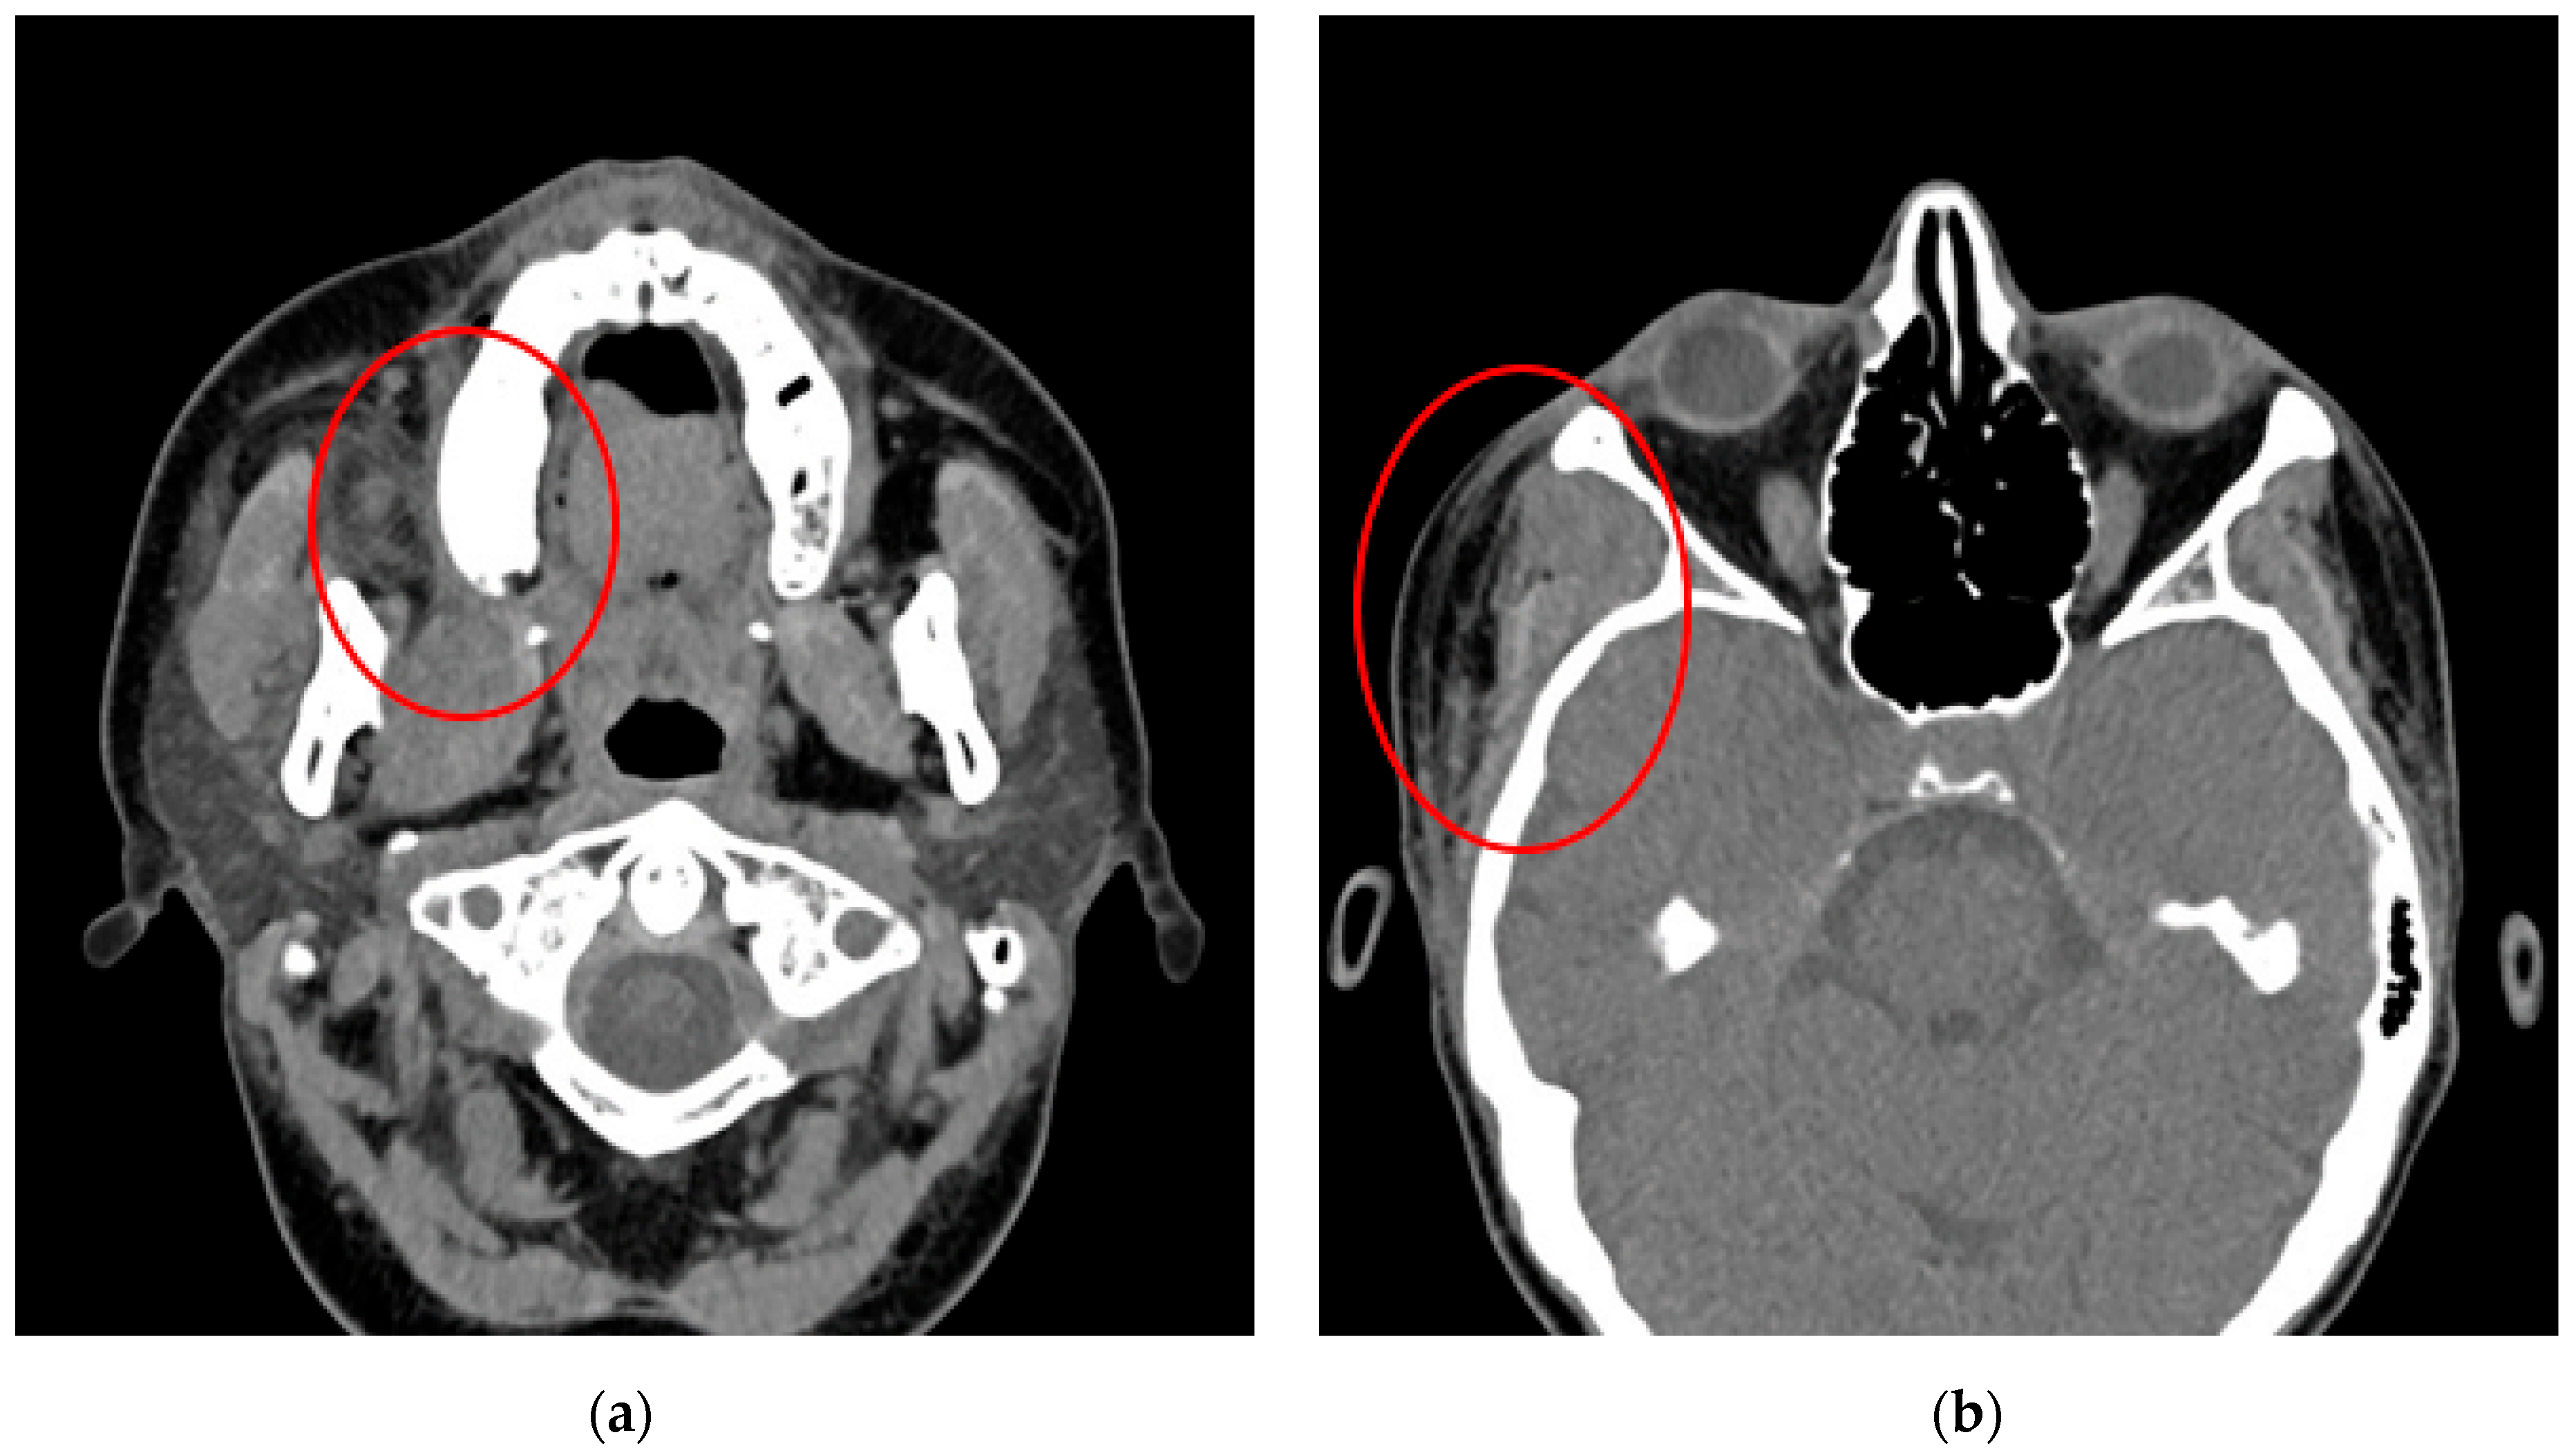

3.1.1. Case No. 1

3.1.2. Case No. 2

3.1.3. Case No. 3